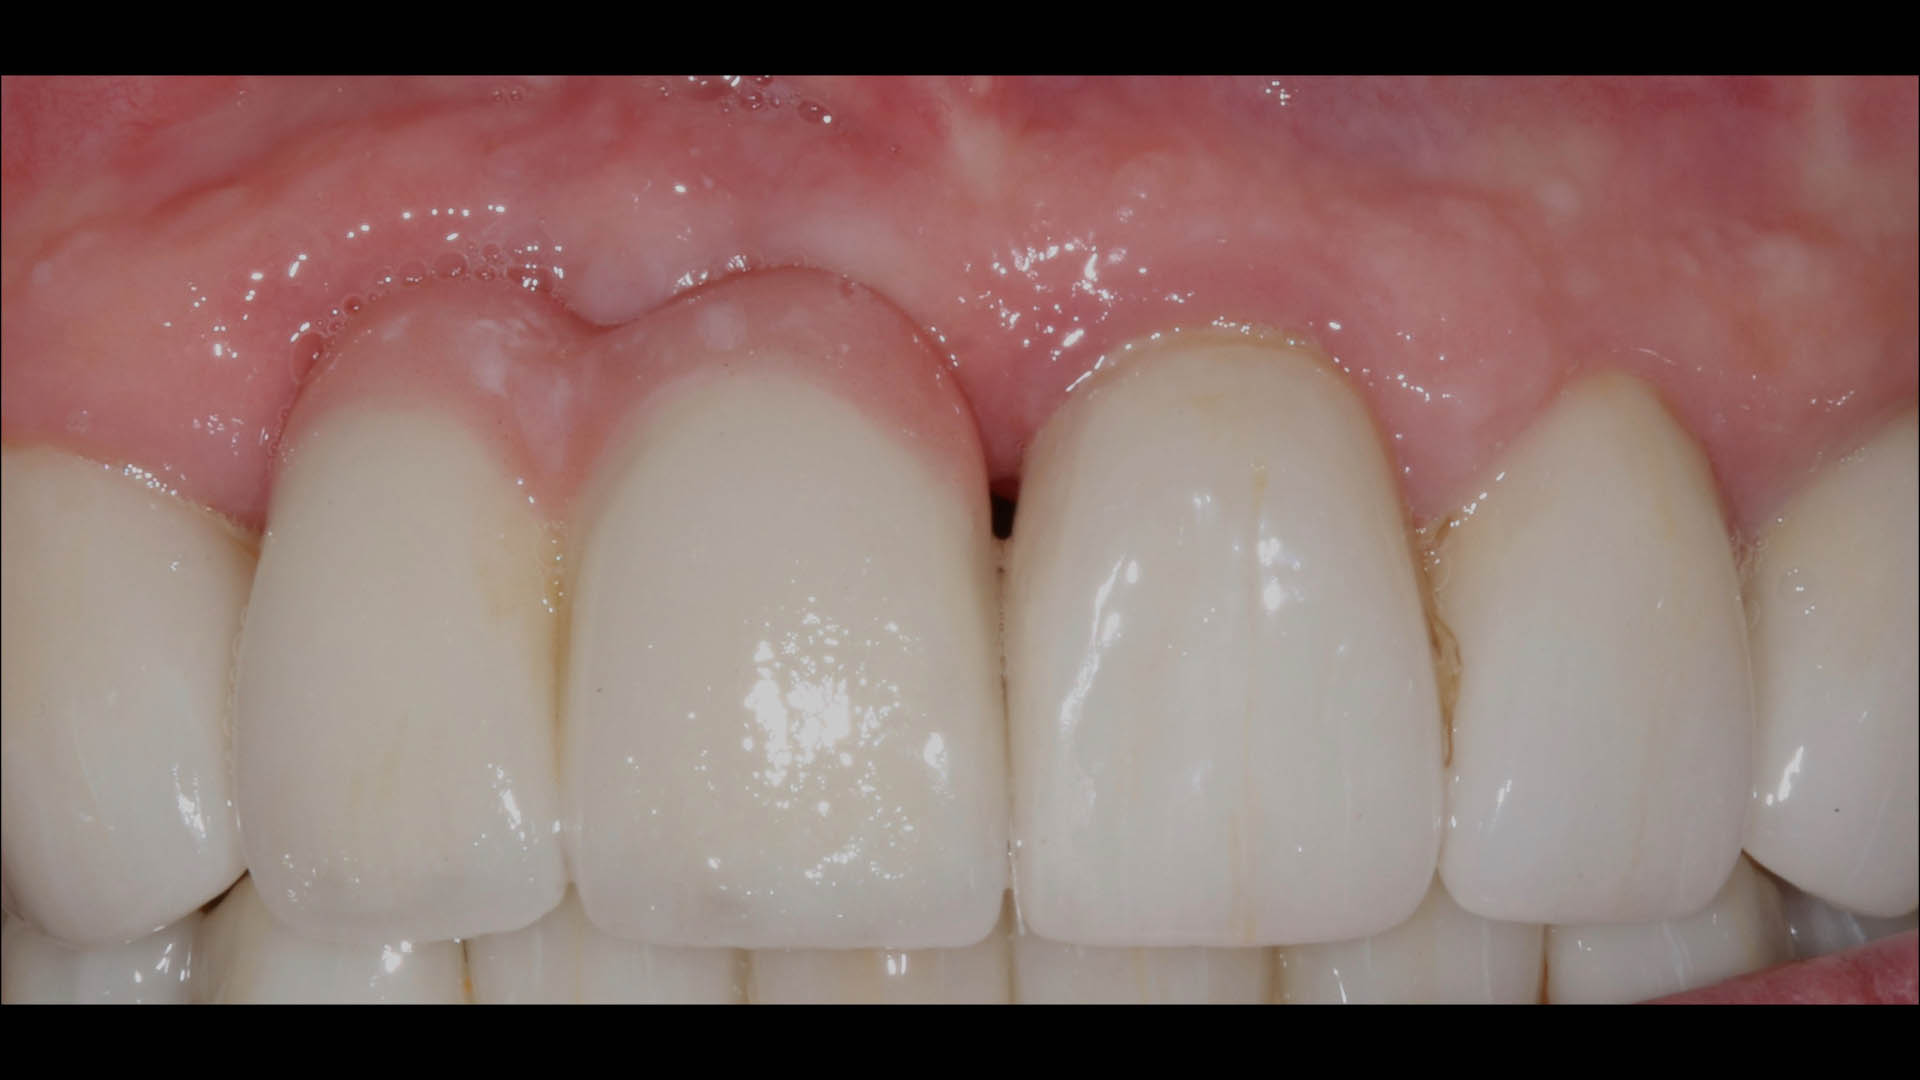

Take a glimpse into the magic of Coral Gables Dentistry through our before and after pictures. See firsthand the incredible smile makeover transformations that have brought confidence and joy to our patients.